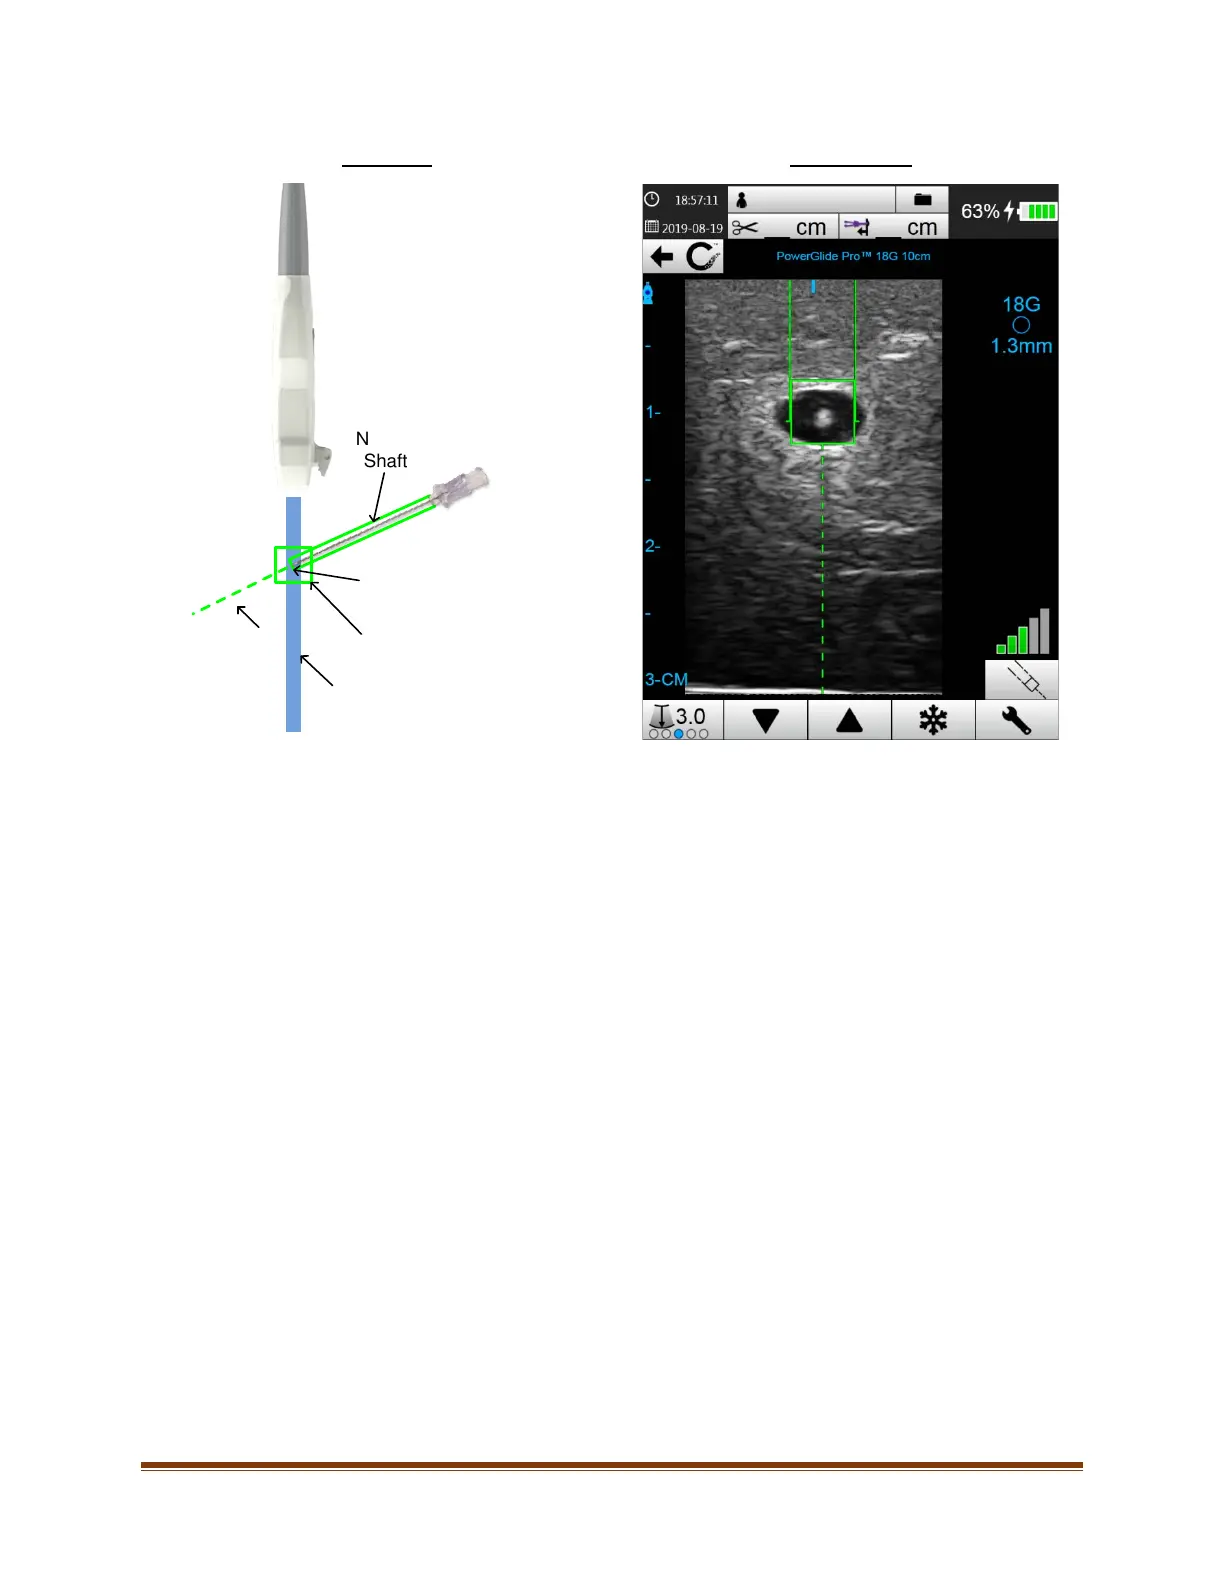

Actual View On-Screen View

Needle

Shaft

Needle Tip

Ultrasound Beam

Trajectory

Intersection Window